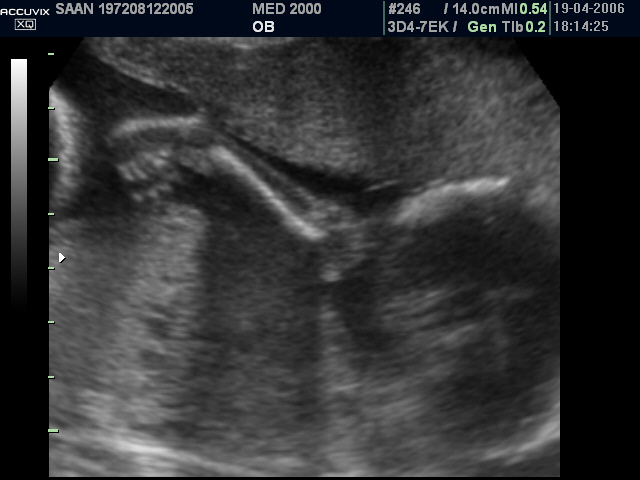

Le anomalie scheletriche più comuni sono le anomalie del raggio radiale: ipoplasia o aplasia del radio, pollice a tre falangi, mano torta, a volte assenza del pollice.

Brons, J. T. J., Van Geijn, H. P., Wladimiroff, J. W., Van der Harten, J. J., Kwee, M. L., Sobotka-Plojhar, M., Arts, N. F. T. Prenatal ultrasound diagnosis of the Holt-Oram syndrome. Prenatal Diag. 8: 175-181, 1988.